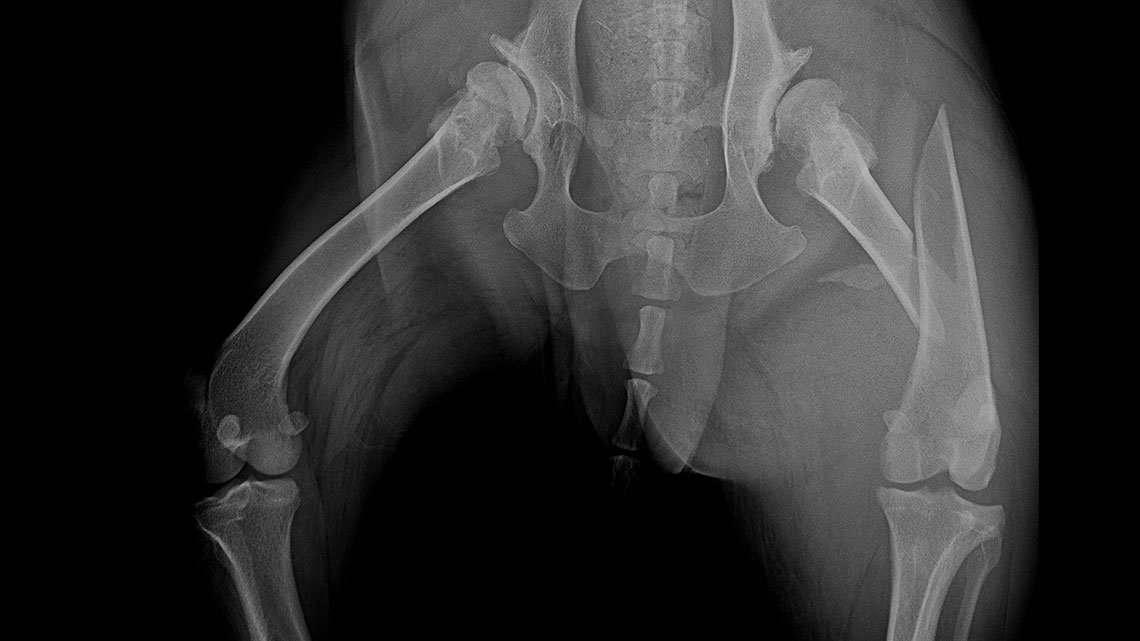

The NEW precontoured polyaxial locking TPLO plate family

07 September 2021

Cheetah (Acinonyx jubatus) in the surgery room

26 July 2021

Fine-tuned… mini devices for mini animals

23 July 2021

Combination of polyaxial locking plating and medullary pinning to treat multiple unstable fractures

21 July 2021

Shar-pei, cruciate ligament rupture surgery

16 June 2021

Nightmare for all of us: diastal humeral Y-fracture in a large active dog (German Shepherd)

07 May 2021